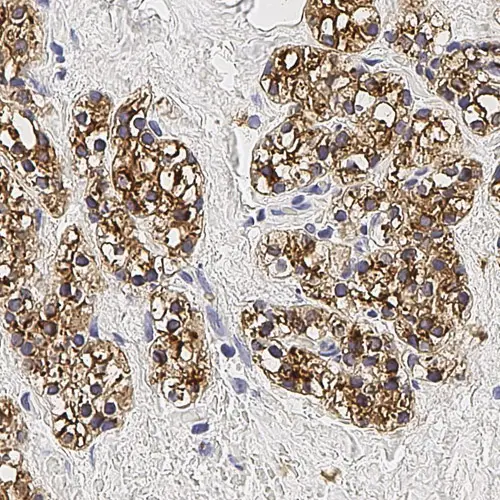

Human parathyroid adenoma: immunohistochemical staining for Parathyroid Hormone. Note membrane/cytoplasmic staining of tumor cells. Parathyroid Hormone: clone 105G7

O hormônio paratireoide é o regulador mais importante dos níveis de cálcio no sangue. As células tronco são as células mais abundantes na glândula paratireoide e são responsáveis pela secreção do hormônio paratireoide. Anticorpos para o hormônio paratireoide juntamente com anticorpos para tireoglobulina são úteis em estudos para diferenciar lesões derivadas da paratireoide de lesões derivadas da tireoide.